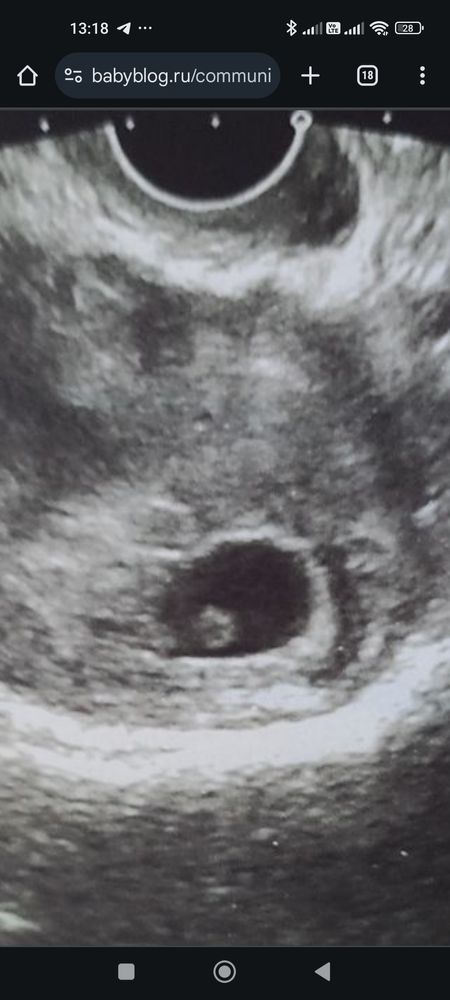

Изображение В первую беременность такое же яйцо было 🥚😃 не переживайте